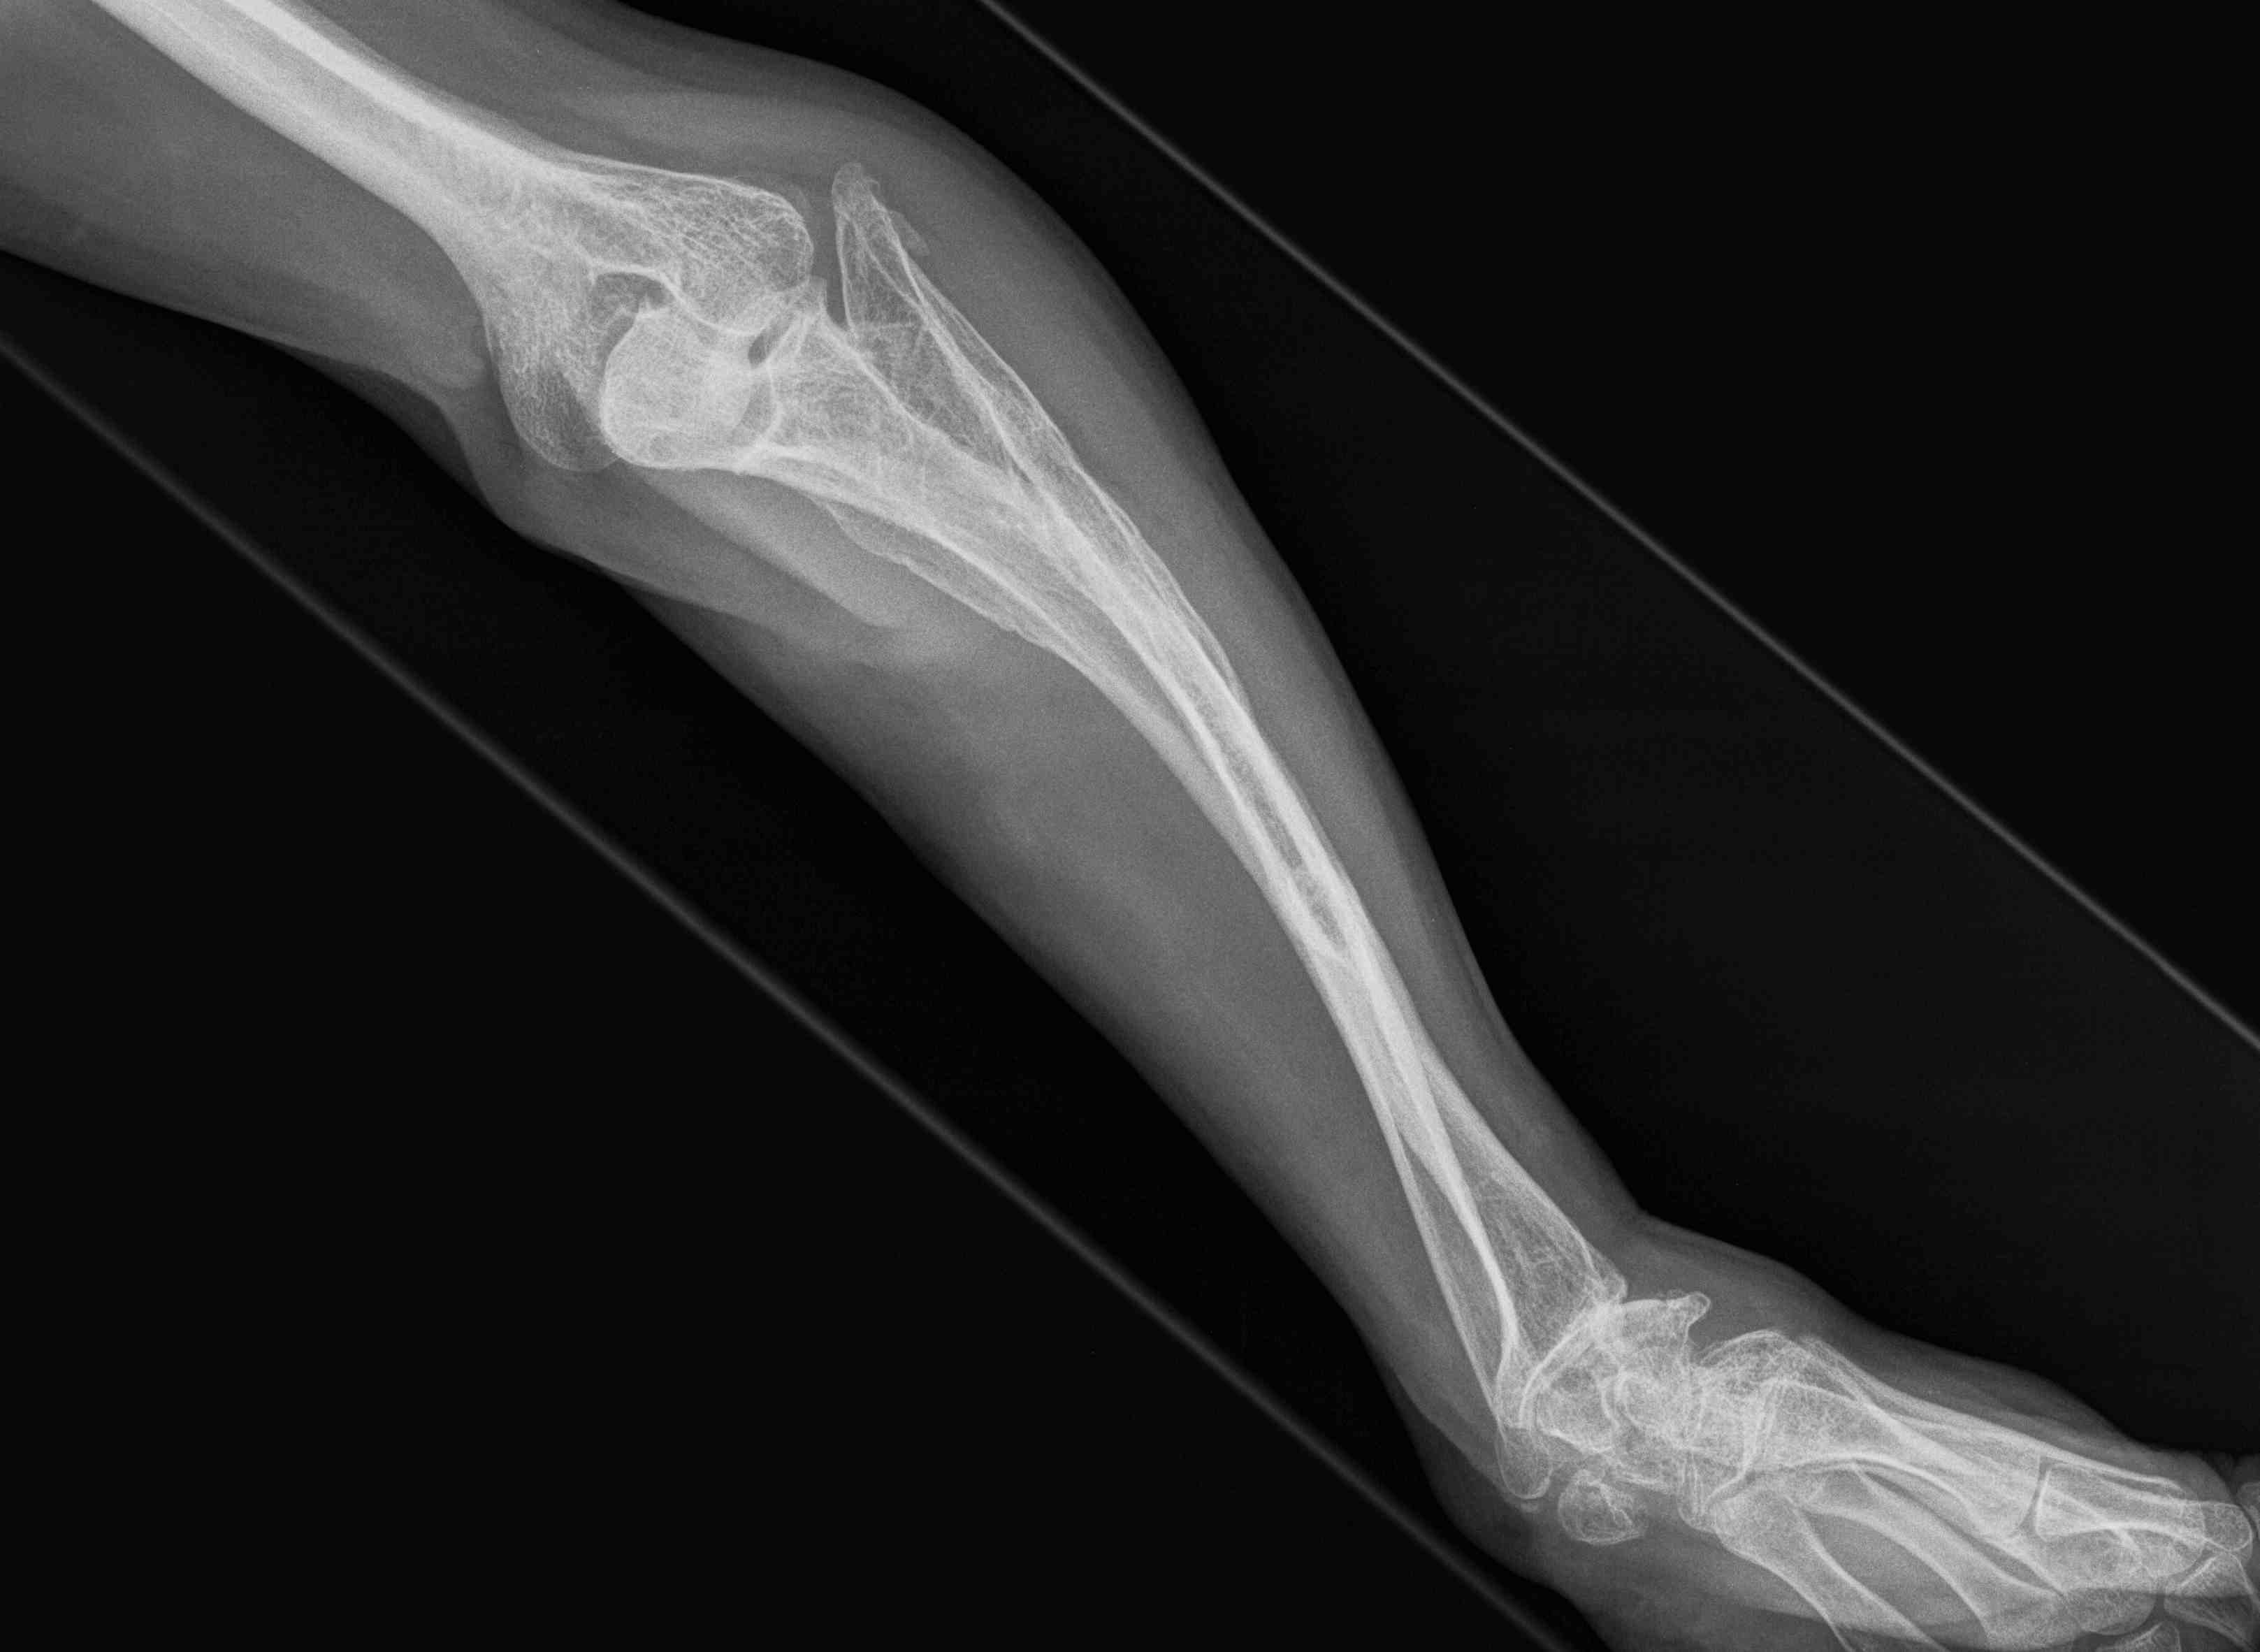

Frequent multilevel fractures with limb deformity

- tibia

- femur

- forearm